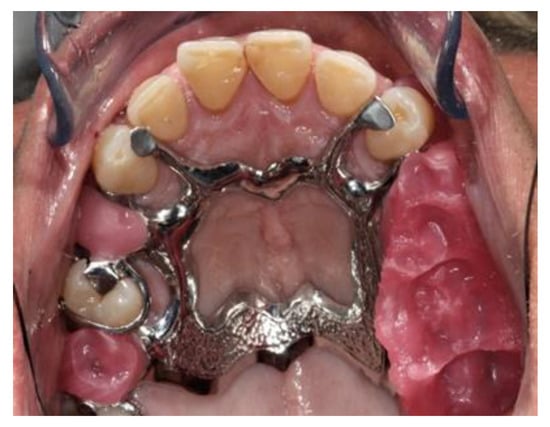

During the fifth appointment, both the prostheses were delivered without having to do any retouching (Figure 19 and Figure 20), and the following clinical evaluations were performed:

Figure 19. Finished and polished prosthesis realized with the analog procedure.